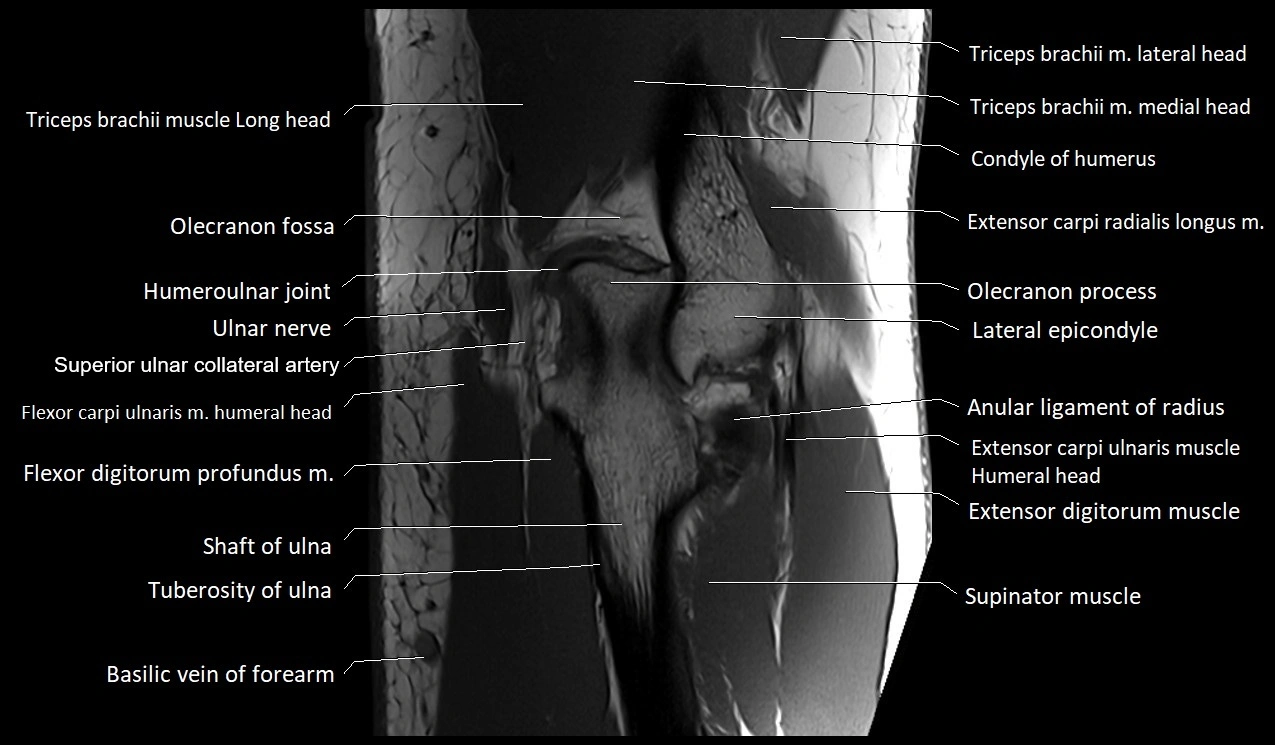

MRI image

image